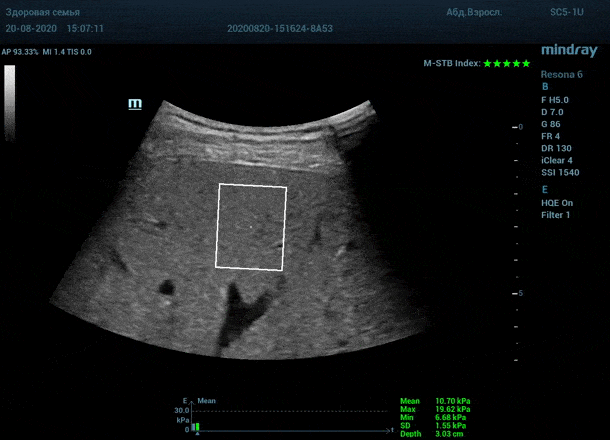

Приводим видео пример: использованы 3 точки доступа печени, каждое значение графика получено прицельным выстрелом HQ Elasto и собрано в единый тренд. В результате анализа 10 значений получен удивительно точный результат - статистический разброс  3.5 % IQR/Med.